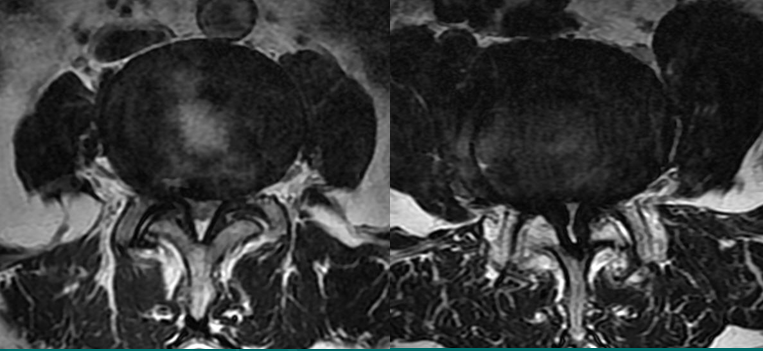

一个健康的45岁男性的L4椎间盘的轴状面观。

髓核区及周围的纤椎环区。

靠近L5神经根的椎间盘后缘的凹度,这是正常健康椎间盘的象征。

L4发出神经根更靠侧方一点。这就不难理解为什么如果有大的椎间盘突出或椎管狭窄,发出神经根L4及过往神经根L5将同时受压。

在此图中,可清楚地看到悬挂在硬膜囊内的细小的神经根(L5神经根及S1神经根),它们以不完全有绪地状态排列着。注意,神经孔是很开阔的(浅黄色区),表明没有因邻近椎间关节问题形成在的椎管狭窄。T2加权象对于察看退化性椎间盘病是最好的,因为T2像将富含水份的结构表现为亮白色, 含水少的区域表现为黑色。